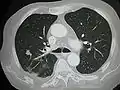

سرطان منتشر في الرئتينMark.png.webp)

- الرئتين: السعال، ونفث الدم وضيق التنفس[6]